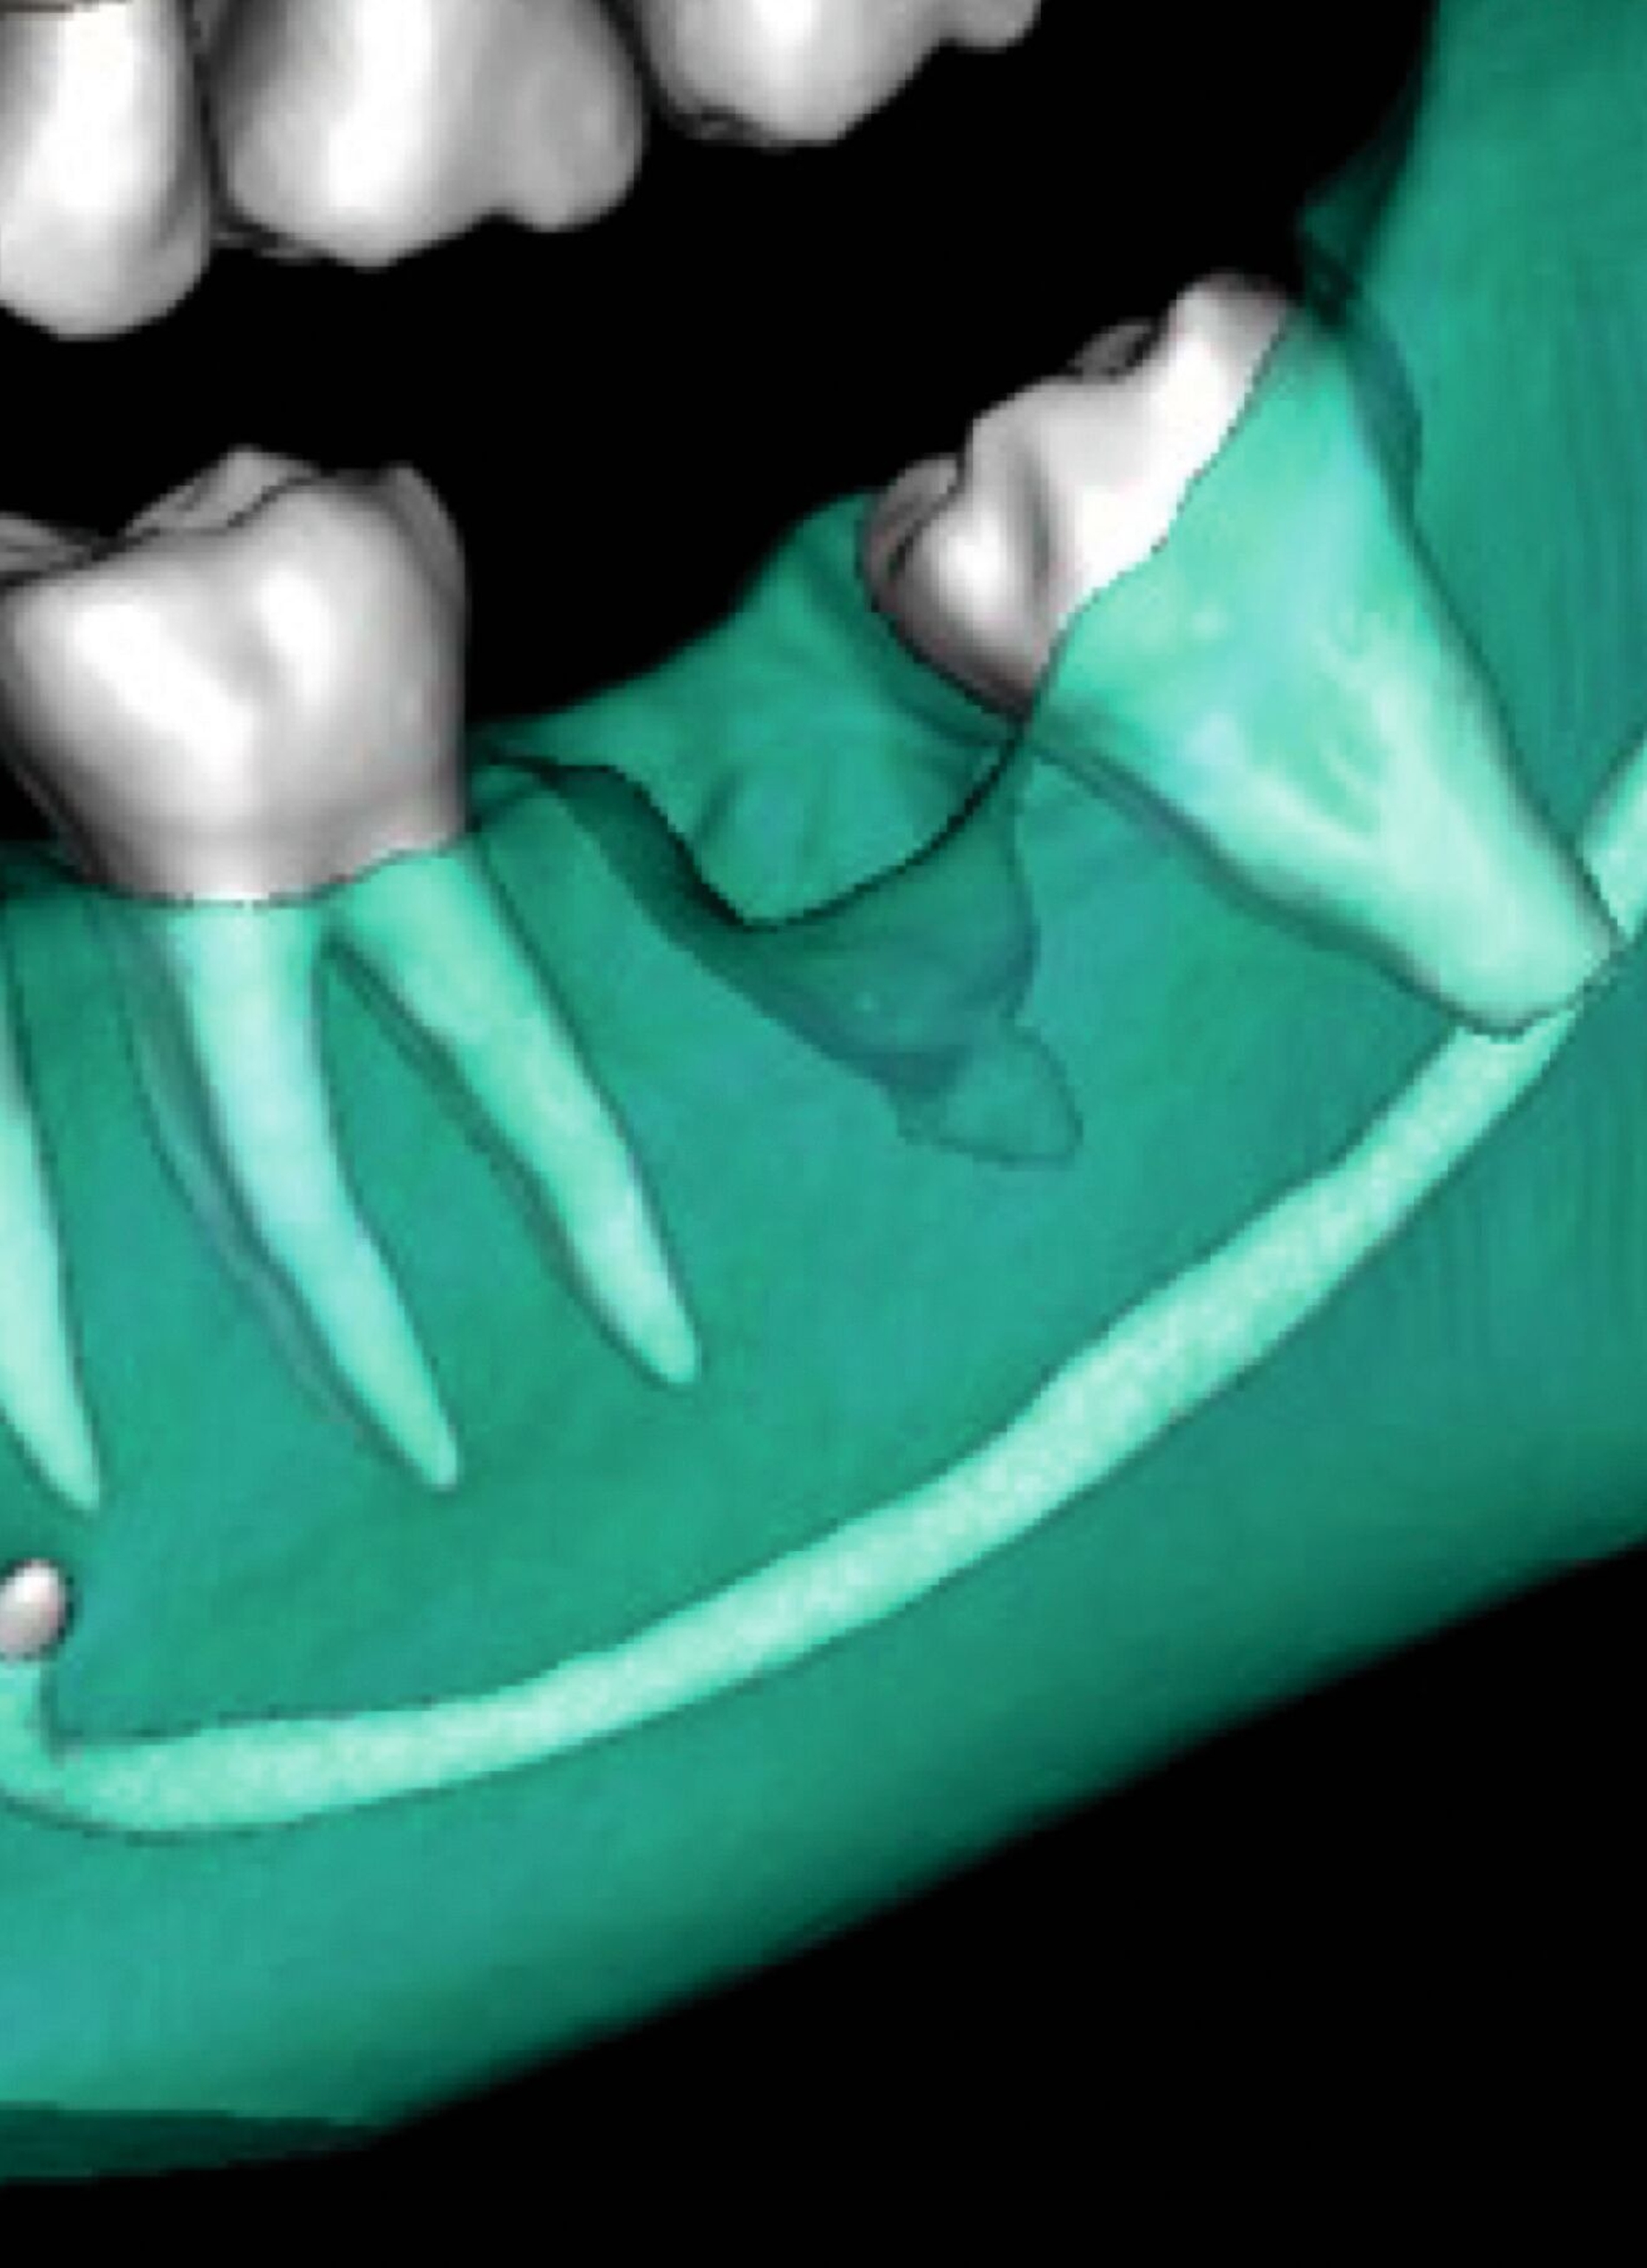

In Absprache mit dem/der zahnärztlich beziehungsweise chirurgisch tätigen Kollegen/in kann die Kieferorthopädie durch Umsetzung verschiedenster 3-D-gedruckter Elemente eine Hilfe in interdisziplinären Behandlungen bieten. Am Beispiel der Zahntransplantation ermöglicht der 3-D-Druck zuvor im DVT segmentierter Zähne eine passgenaue Vorbereitung des Transplantationsbettes (Abbildung 6a). 3-D-gedruckte Zähne können darüber hinaus als Lückenhalter während der kieferorthopädischen Behandlung dienen (Abbildung 6b), bevor eine definitive Versorgung durch den/die zahnärztliche/n Kollegen/in erfolgt.

Weitere Beispiele beinhalten hochkomplexe Behandlungsfälle multipler Zahnanlagen. Während die Extraktionsentscheidung und Absprache mit dem/der chirurgisch tätigen Kollegen/in allein auf Basis der Bildgebung oft limitiert ist, erleichtern 3-D-gedruckte Modelle des segmentierten DVTs sowohl die Entscheidung als auch die Absprache und ermöglichen darüber hinaus eine genauere Planung des chirurgischen Vorgehens (Abbildung 6c). Gleiches betrifft parodontalchirurgische Eingriffe, in denen sogenannte „Cutting guides“ eine zuvor digital geplante Gingivektomie ermöglichen (Abbildung 6d). Im Bereich der Freilegung verlagerter Zähne können Schablonen dem/die chirurgisch tätigen Kollegen/in sowohl die Freilegung des Zahnes (Abbildung 6e) als auch die Anbringung eines Attachments (Abbildung 6f) erleichtern und dabei die kieferorthopädisch gewünschte Attachmentposition passgenau übertragen.